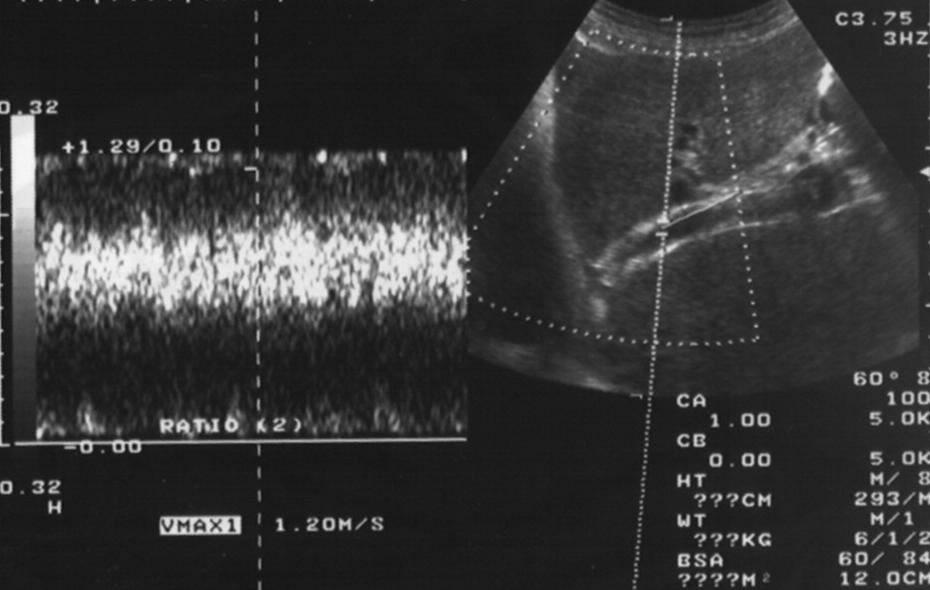

多普勒超声随访覆膜支撑架

TIPS术后随访 1. 术后立即随访(实时疗效判定、技术成功判定)

2. 后续随访

随机对照研究,裸支撑架 vs PTEF 覆膜支撑架【10】

相同作者第二次随机对照研究像是2年开通率,覆膜支撑架和裸支撑架分别为76%,36%【11】。